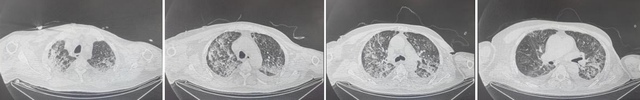

患者9日后复查CT

经重症医学科全体医护人员精心治疗与护理,患者各器官功能逐步恢复,氧合情况显著改善。9日后成功脱机拔管,复查胸部CT显示双肺渗出明显吸收;两个月后门诊复查CT显示,肺功能进一步好转,患者及家属倍感欣慰。